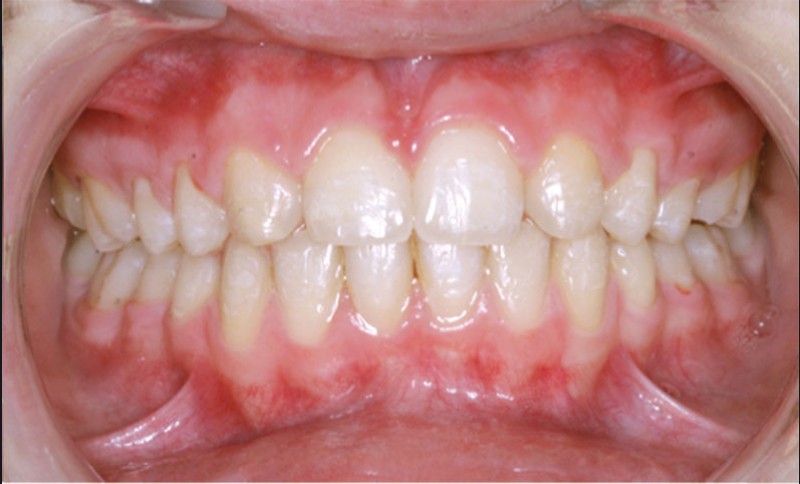

Ludivine T. âgée de 12 ans et demi présente une agénésie des deux incisives latérales maxillaires dans un contexte occlusal de classe II division 2 (fig. 1 à 3).

Les vues endo-buccales (fig. 2) montrent la classe II division 2 occlusale associée à une forte supraclusion incisive et l’évolution spontanée de 13 et 23 pratiquement en place de 12 et 22. Il persiste cependant un diastème disgracieux entre 13 et 11.